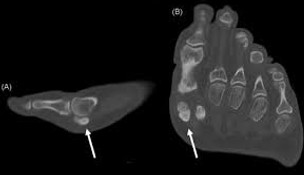

Fracture du sésamoïde du gros orteil

Motif de consultation :

Douleur localisée sous l’avant-pied, particulièrement au niveau de la base du gros orteil, aggravée par la marche ou la course, et parfois accompagnée d’un gonflement.

Objectif de la prise en charge :

Soulagement de la douleur, amélioration de la fonction de l’avant-pied, et optimisation de la consolidation osseuse, avec immobilisation. Approche conservatrice en priorité.